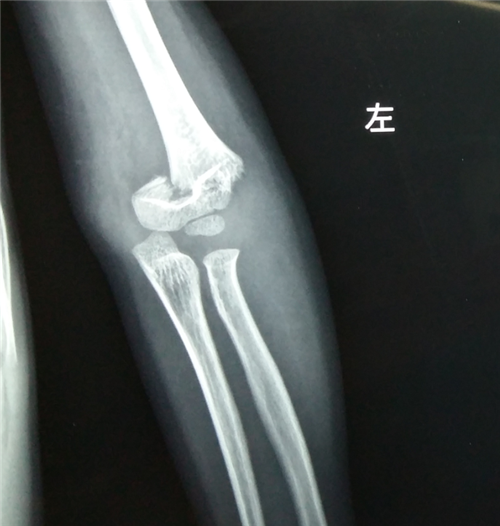

网站首页 » 科室介绍 » 创伤急救 » 各关节创伤